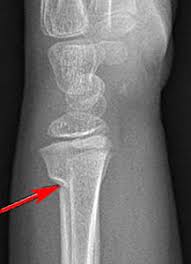

Https Encrypted Tbn0 Gstatic Com Images Q Tbn And9gcs3rkcv6nhn Nzxdau59qvnq7grubo0 Lbikskhfk9l0d9l8eu2 Usqp Cau

Https Encrypted Tbn0 Gstatic Com Images Q Tbn And9gcs3rkcv6nhn Nzxdau59qvnq7grubo0 Lbikskhfk9l0d9l8eu2 Usqp Cau from